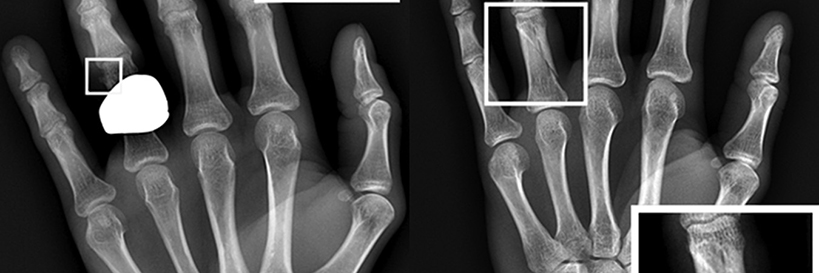

Yes. Every Patient First is equipped for routine digital x-rays of the chest, abdomen, spine, skull and extremities. To learn more about digital imaging at Patient First, please visit our X-rays page.

This means if you come in with a fracture, for example, we can confirm the break, put a splint on it, and, if necessary, arrange for you to see a specialist. Our on-site x-ray also helps our physicians diagnose conditions such as pneumonia, kidney stones, and dislocations.